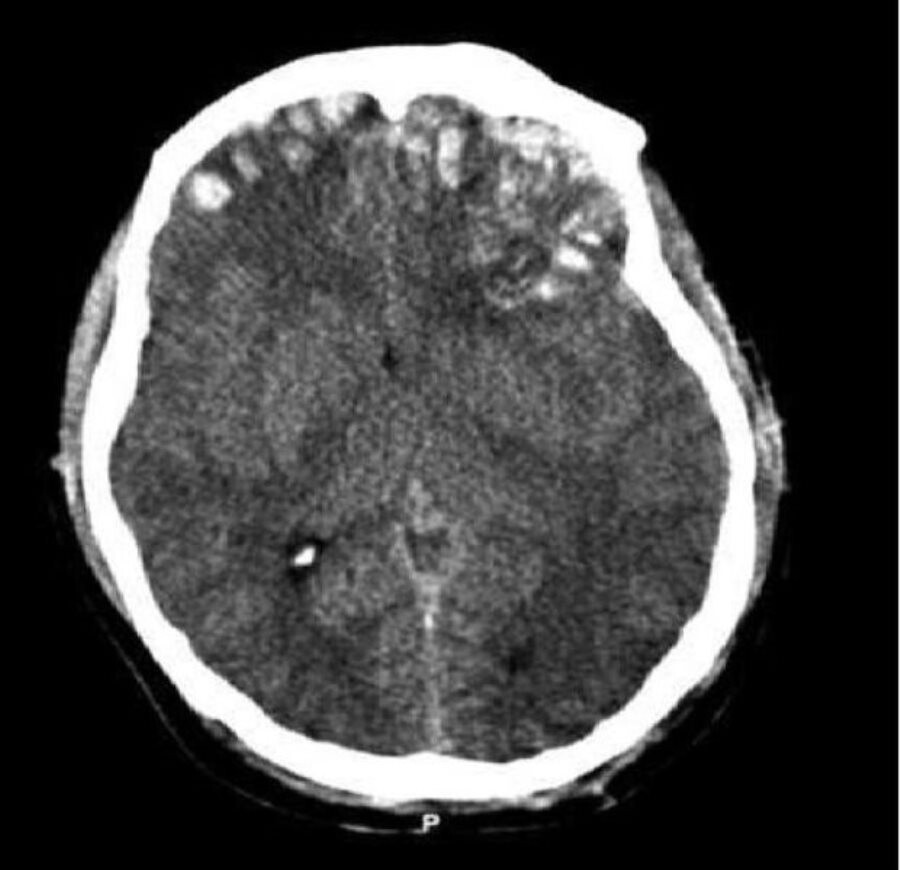

Los traumatismos craneoencefálicos son una de las consecuencias directas más severas de un accidente. El 70% de los TCE tienen su origen en un accidente de tráfico y las personas afectadas son principalmente jóvenes, han detallado estos profesionales.

La atención médica urgente es fundamental en un traumatismo de esta índole para alcanzar una estabilización clínica inicial, detallan. A partir de ahí, el pronóstico va a estar condicionado en gran medida por el tratamiento de rehabilitación, tanto por la calidad del mismo, como la intensidad y el momento de inicio. Tal y como explica el Dr. Joan Ferri, Director del Servicio de Neurorrehabilitación de Hospitales Vithas Nisa: «las consecuencias clínicas de un TCE son diversas. Frecuentemente, abarcan distintas esferas de la persona, como el intelecto, la movilidad o el carácter. Por ello, un correcto abordaje rehabilitador requiere un equipo de profesionales con experiencia y unos recursos especializados».

Según datos de la Federación Española de Daño Cerebral (FEDACE), en España se producen aproximadamente 35.000 ingresos hospitalarios por Traumatismo Craneoencefálico y alrededor de 4.500 de estas personas reciben el alta con alteraciones funcionales múltiples (físicas, sensoriales, cognitivas, conductuales, etc.). Entre ellos, aproximadamente, el 10% de los pacientes que han sufrido un traumatismo craneoencefálico grave, después del primer mes, se encuentran sin recuperar la conciencia.

Prácticamente, la totalidad de los traumatismos graves pierde la conciencia tras el accidente de tráfico y su recuperación dependerá de la gravedad de las lesiones siendo el periodo de coma un marcador pronóstico de la recuperación del paciente, según informa Carolina Colomer, Médico Rehabilitadora y Directora Clínico del Servicio de Neurorrehabilitación. Hospitales Vithas Nisa / COECS.